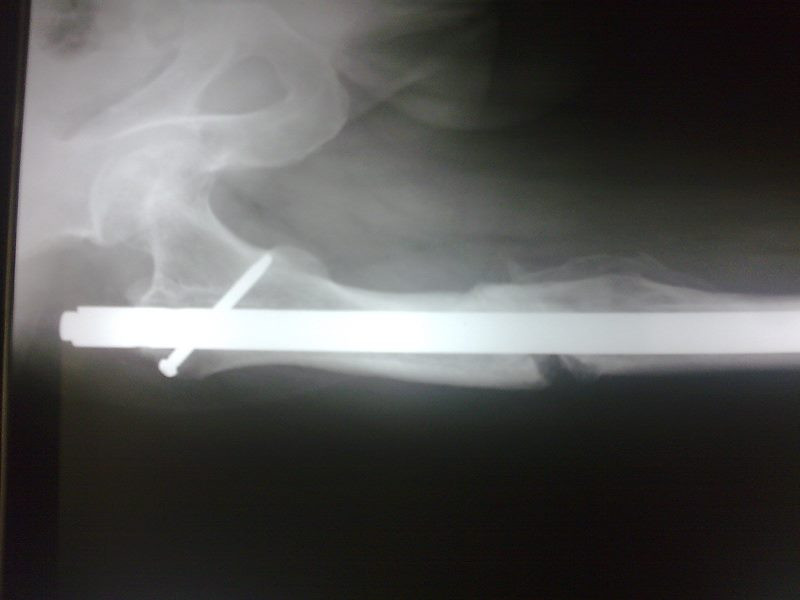

Radiografías con enfoque en fisiatría

Envíado por Dr. Hernán Darío Sánchez Ramos